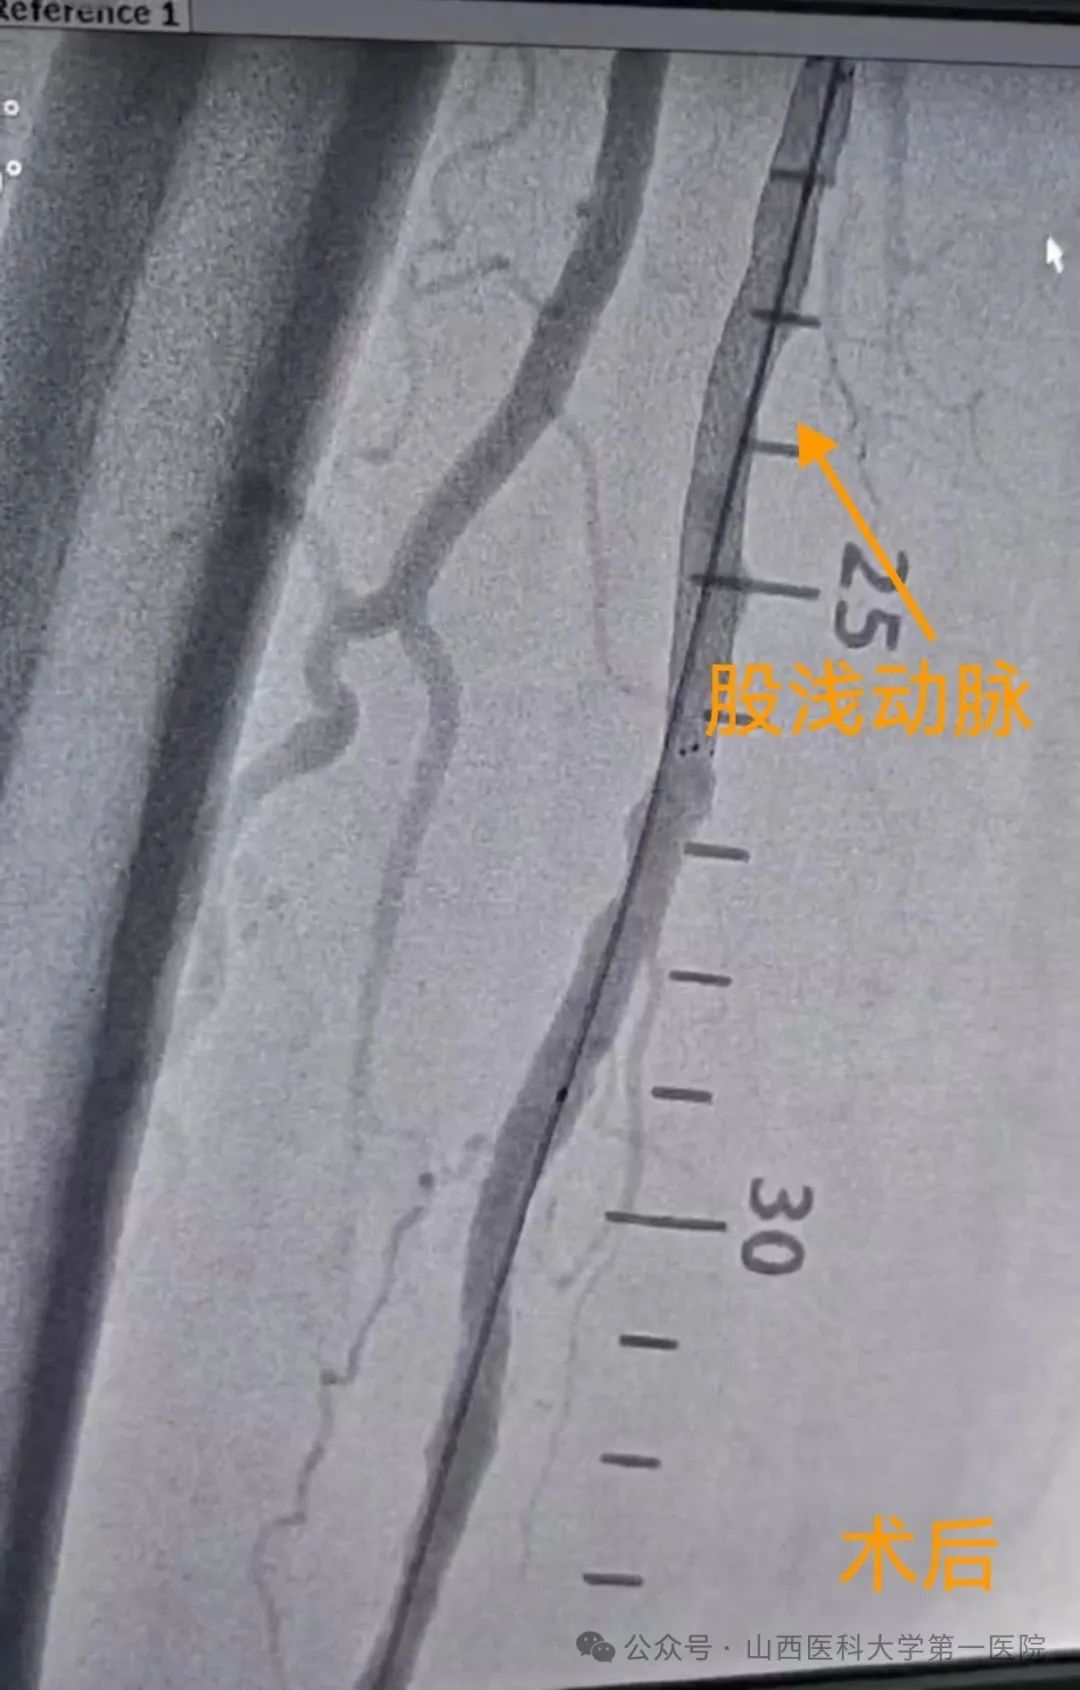

血管外科手术室内,一场与时间、风险和生命质量的“静默较量”悄然展开,血管外科团队为多种基础疾病缠身的93岁梁奶奶开展了手术风险极高的左股动脉穿刺+右下肢动脉造影+右股浅动脉球囊扩张成形术+支架植入术,打通了闭塞的下肢血管。

“老人的血管像干枯的树枝,脆而易断,我们要在这样的血管里完成导丝通过、球囊扩张和支架植入,每一步都必须稳、准、细。”血管外科主任王贵明说。凭借多年的临床经验和团队协作,他带领手术团队精准操作,成功完成导丝穿通、球囊扩张、支架植入全过程,术中出血不足30ml,老人生命体征始终稳定。